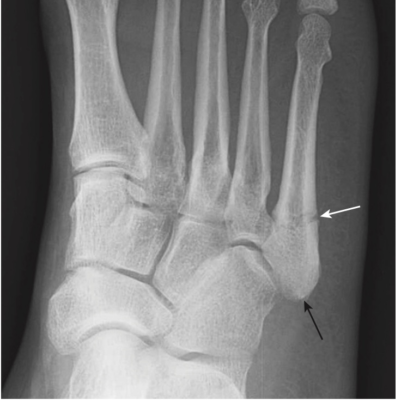

- Gãy Jones là một gãy ngang của xương bàn đốt chân ngón út cách nền xương khoảng 1 đến 2 cm, do gập lòng bàn chân và cổ chân vẹo trong. Gãy xương Jones thường lâu lành hơn so với gãy bong mảnh bám nền xương bàn đốt ngón chân út (là loại gãy thường gặp hơn, dancer’s fracture) (Hình 12).